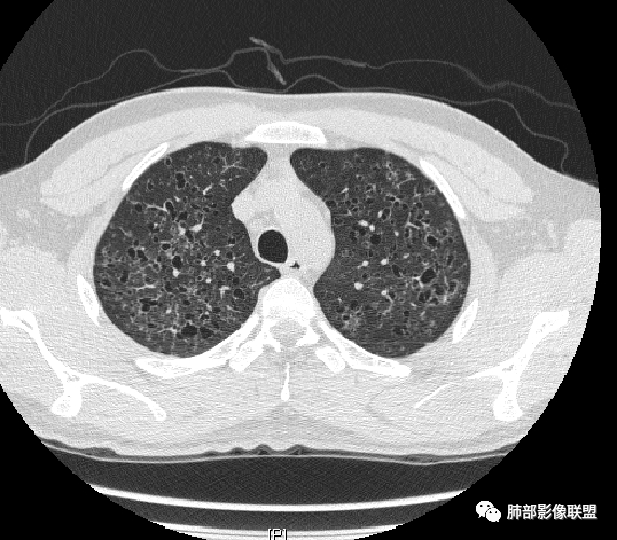

秦化君: 晨读 双肺不均匀散在多发囊状影,大小不等,部分囊形态欠规整,壁薄均匀,部分囊胸膜下平行。双肺少许斑片状磨玻璃影,边缘模糊。考虑BHD综合征。鉴别PCP,LIP。

红日初升: 中年女性,双肺多发气囊,背景干净,大小不一,下肺韧带旁较大,考虑BHD,鉴别LIP、LAM

宇宙: 中年女性,两肺多发大小不等薄壁囊状影,两肺纵膈胸膜下分布明显,考虑BHD,鉴别LAM

这个病例目前影像特点,多囊,囊主要位于下肺,胸膜下及小叶核心为主

伴随少许索条,而且这些病灶与囊不一定有相关性

囊的分布,PLCH基本可以排除

囊壁薄且均匀,光滑,形态规则,基本除外恶性

单纯囊,无斑片及其他实性病灶,感染不支持,可能的是:LAM、BHD、LIP

从囊的分布、大小,BHD可能性可能大一些,但是LIP、LAM都可以这样表现,具体诊断应该是这三种之一,影像缩小到这里我觉得就差不多了,结合临床考虑就行,不支持靠影像强下结论。

临床诊断BHD综合征需要满足一个主要或两个次要标准。主要标准包括:1、皮肤上至少发现5个纤维滤泡瘤,至少1个组织学证实;2、致病的FLCN种系突变阳性。次要标准:1、多发肺囊肿,双侧基底部,有或无自发性气胸;2、肾癌,起病早(<50岁)或多灶性或双侧;3、 BHD综合征一级亲属。BHD主要影像表现特征:1、两肺内肺囊肿:80%以上的BHD患者会出现肺内囊肿,且倾向于基底部近胸膜下分布,特别是纵隔侧肺膜下,囊肿形状不规则、囊肿可大可小,肺内囊肿多毗邻肺下动脉或静脉近端,胸部CT上囊肿分布和特点对诊断有提示意义。2、继发自发性气胸:BHD患者发生气胸风险是正常人的5倍,BHD患者的气胸发生率约为1/4,气胸复发率则高达59%。3、肾肿瘤:(常为双侧性、倾向于嫌色细胞组织学亚型)4、皮肤表现:(为面、颈部纤维性毛囊瘤、毛盘瘤)